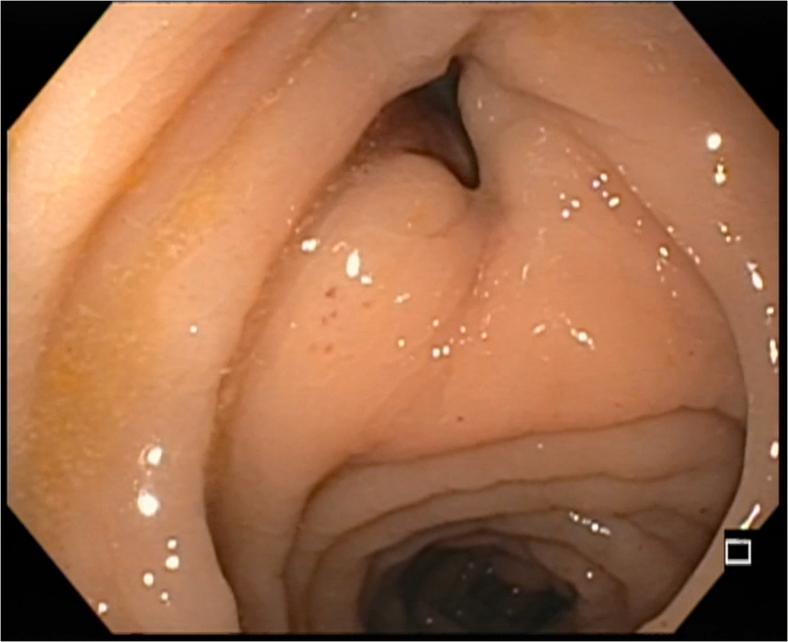

Video 1Use of a novel endoscopic tack and suture system for the management of pancreatocolonic fistula.

视频1:使用新型内镜钉合与缝合系统治疗胰结肠瘘